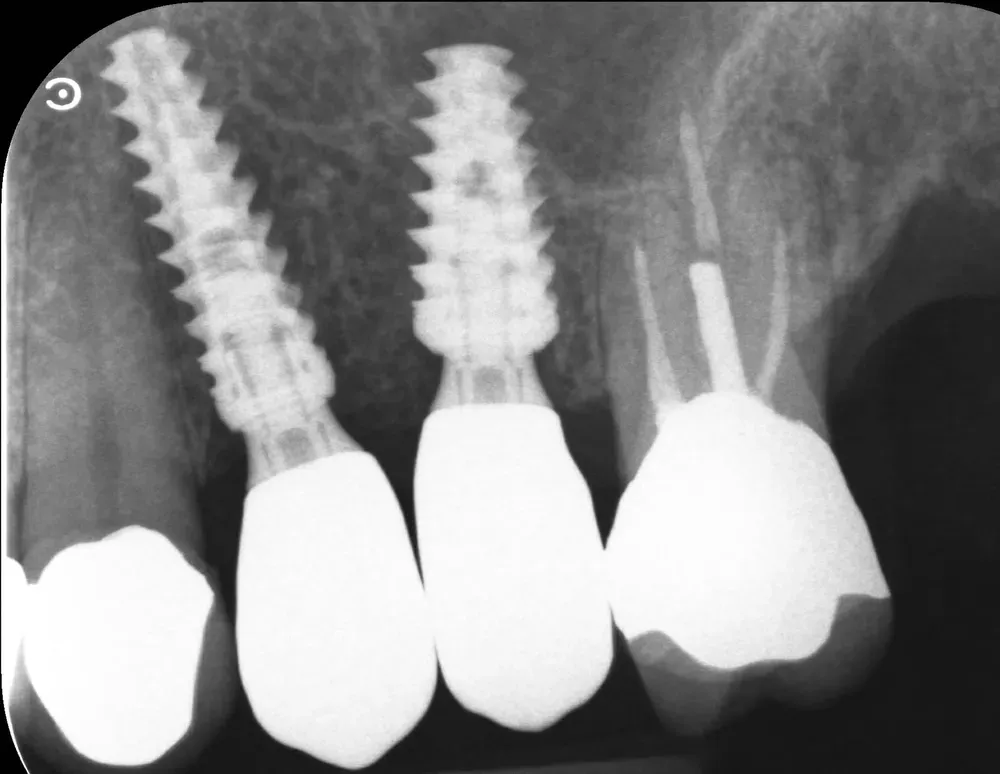

Di seguito, le radiografie periapicali mostrano gli impianti appena inseriti e gli abutment con i provvisori.

Rx Periapicale Post-op

Rx Periapicale con abutment e provvisori